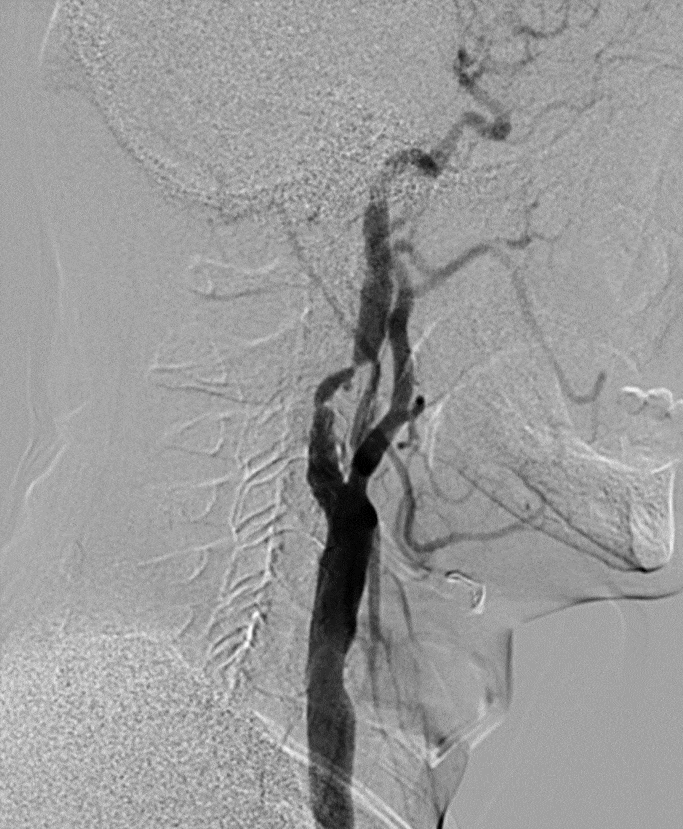

男,73岁,因“发现左侧颈内动脉狭窄1天”入院。既往高血压病史;查体:无异常。

7F(081) 指引输送Protégé 10-7-40

输送顺畅,且仍可造影

术毕造影